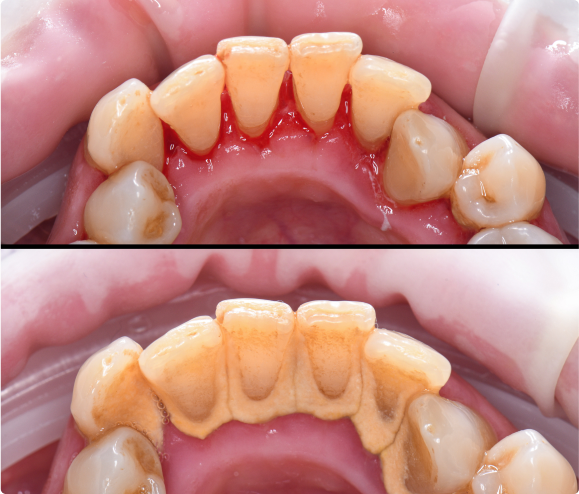

• Gingivitis is a milder form of gum disease that can present itself as bacterial inflammation of the gums resulting in redness, some swelling and bleeding.

• Good news! Gingivitis can be easily treated and reversed with regular dental cleanings and proper oral hygiene.

What Happens if I Do Not Treat My Gingivitis?

• If Gingivitis is left untreated, bacteria continues to build and damage the tissues and bone surrounding the teeth, resulting in “Periodontitis” or inflammation of the hard tissues. With Periodontitis, the bacterial damage results in periodontal pockets that can become infected and result in bone and connective tissue loss which ultimately lead to tooth mobility and tooth loss.